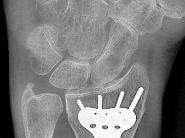

A 12-year-old boy presents with left thigh pain, an antalgic gait, and an externally rotated left lower extremity. Radiographs demonstrate the pathology shown. Which of the following is considered an absolute indication for prophylactic pinning of the asymptomatic, contralateral hip in a patient presenting with Slipped Capital Femoral Epiphysis (SCFE)?

Correct Answer: Underlying endocrine disorder (e.g., hypothyroidism)

Explanation:

SCFE is characterized by a displacement of the proximal femoral epiphysis. Prophylactic pinning of the contralateral hip is somewhat controversial but generally recommended in patients with a high risk of subsequent contralateral slip. Absolute indications or highly strong recommendations for prophylactic contralateral pinning include an underlying endocrine disorder (such as hypothyroidism or growth hormone deficiency), renal osteodystrophy, previous radiation therapy, and presentation at a very young age (e.g., < 10 years). Endocrine disorders dramatically increase the risk of bilateral involvement, often occurring simultaneously or sequentially.